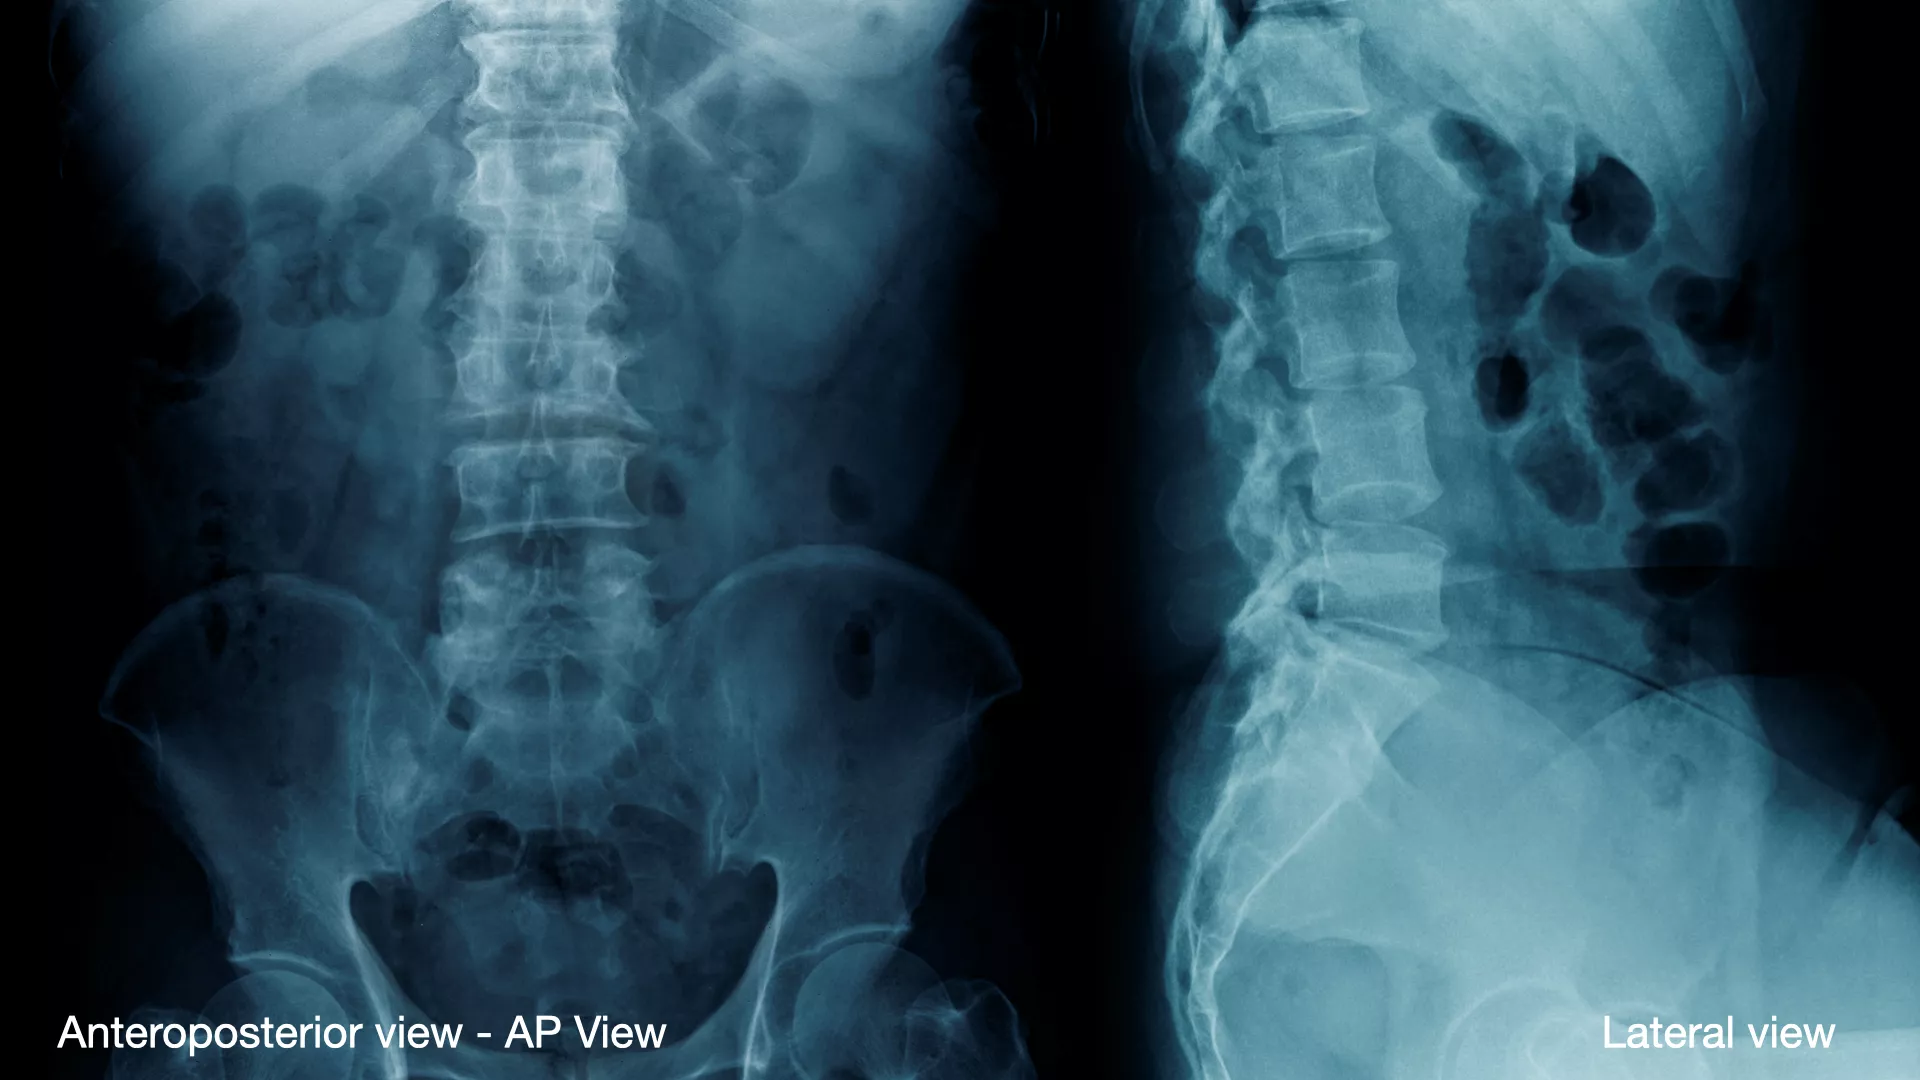

ท่าตรง (Anteroposterior View - AP View)

- ลักษณะ : ผู้ป่วยจะอยู่ในท่ายืนหรือนอนหงาย แล้วเจ้าหน้าที่รังสีวิทยาจะถ่ายภาพจากด้านหน้า

- ความสำคัญ : เพื่อประเมินภาพรวมของกระดูกสันหลัง แพทย์จะใช้ท่านี้เพื่อดูแนวกระดูกว่ามีความตรงหรือไม่ และตรวจหาภาวะ กระดูกสันหลังคด หรือ กระดูกสันหลังเคลื่อน รวมถึงดูความกว้างของช่องว่างระหว่างข้อกระดูก

ท่าด้านข้าง (Lateral View)

- ลักษณะ: ผู้ป่วยจะยืนหรือนอนตะแคงเพื่อถ่ายภาพ

- ความสำคัญ : ท่านี้ช่วยให้แพทย์เห็นความโค้งตามธรรมชาติของกระดูกสันหลังในแนวหน้า-หลังได้อย่างชัดเจน และยังใช้เพื่อประเมินความสูงของหมอนรองกระดูก รวมถึงดูว่ามีภาวะ กระดูกสันหลังเคลื่อน ไปข้างหน้าหรือข้างหลังหรือไม่